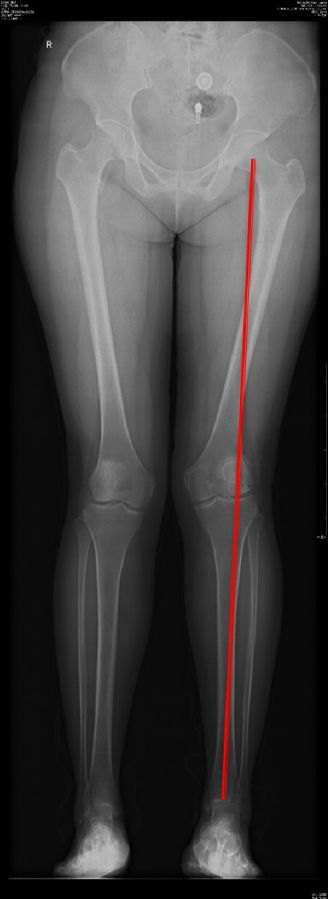

以两例病例展示术前设计的五步。患者一,女性,42岁,左膝疼痛2年,加重1年。

步骤一:判断内外翻畸形

画下肢机械轴,股骨头中心链接踝关节中心判断患者为内翻畸形还是外翻畸形。此患者为外翻畸形。